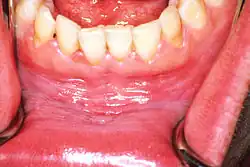

![]() | |

| Leukoplakia on the inside of the cheek | |

Oral leukoplakia is a potentially malignant disorder affecting the oral mucosa. It is defined as "essentially an oral mucosal white/gray lesion that cannot be considered as any other definable lesion." Oral leukoplakia is a gray patch or plaque that develops in the oral cavity and is strongly associated with smoking.[8] Leukoplakia is a firmly attached white patch on a mucous membrane which is associated with increased risk of cancer.[4][5] The edges of the lesion are typically abrupt and the lesion changes with time.[4][6] Advanced forms may develop red patches.[6] There are generally no other symptoms.[9] It usually occurs within the mouth, although sometimes mucosa in other parts of the gastrointestinal tract, urinary tract, or genitals may be affected.[10][11][12]

Homogeneous leukoplakia (also termed "thick leukoplakia")[2] is usually well defined white patch of uniform, flat appearance and texture, although there may be superficial irregularities.[2][9] Homogeneous leukoplakia is usually slightly elevated compared to surrounding mucosa, and often has a fissured, wrinkled or corrugated surface texture,[2] with the texture generally consistent throughout the whole lesion. This term has no implications on the size of the lesion, which may be localized or extensive.[2] When homogeneous leukoplakia is palpated, it may feel leathery, dry, or like cracked mud.[2]

Sometimes leukoplakia of the floor of mouth or under the tongue is called sublingual keratosis,.[19] though this is not universally accepted to be a distinct clinical entity from idiopathic leukoplakia generally,[19] as it is distinguished from the latter by location only.[3] Usually sublingual keratoses are bilateral and possess a parallel-corrugated, wrinkled surface texture described as "ebbing tide".[3]